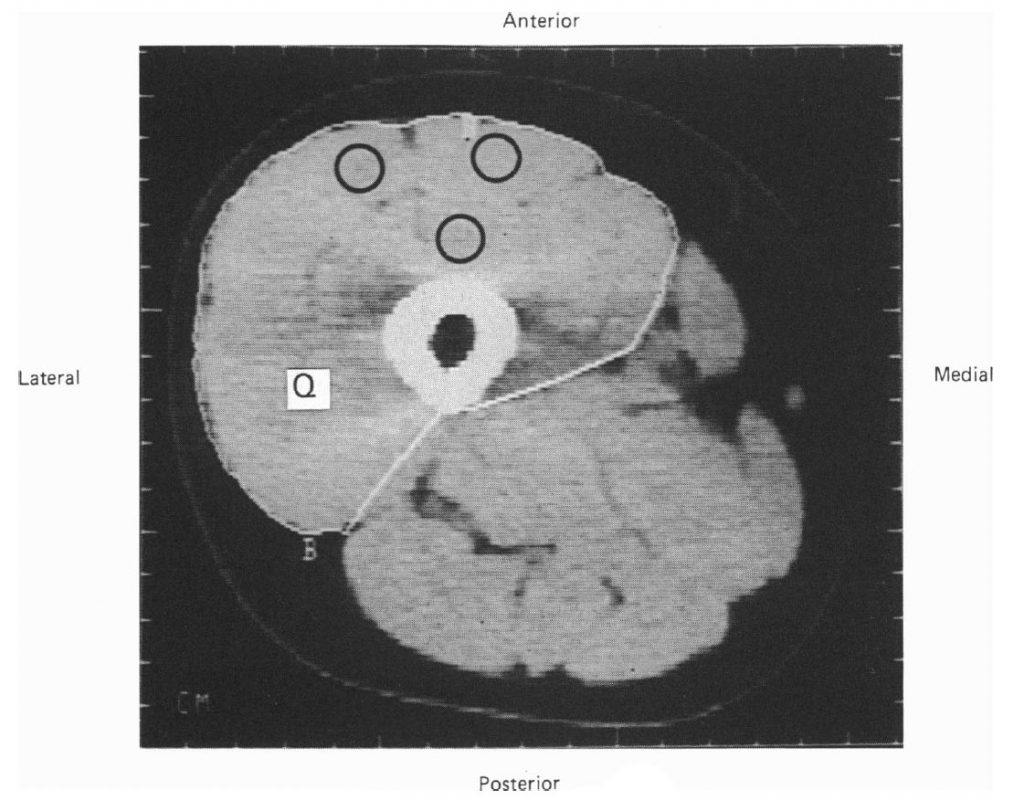

Измерение объема четырехглавой м. бедра. Площадь поперечного сечения четырехглавой была измерена посредством компьютерной томографии (c.t.). Измерения проводились до и после 12 недель тренировки. Все просмотры были выполнены на Philips Tomoscan 310 со временем просмотра 4-8 с и толщиной среза в 9 мм. Чтобы удостовериться, что повторные сканирования проводятся на том же самом месте, на пластиковом листе была изготовлена карта, показывающая на компьютерном томографе область сканирования, связанную с выступами на бедре. Маркеры размещались на ноге, высота от пола до участка просмотра измерялась антропомером Holstan.

Компьютерные изображения были проанализированы посредством разработанной интерактивной системы (Grindrod, Tofts, Edwards, 1983). Оценивалась площадь поперечного сечения четырехглавой мышцы бедра и среднее число Хаунсфилда (единица радиологической плотности; Bulcke, Termote, Palmers, Crolla, 1979). Область четырехглавой мышцы была измерена полуавтоматически посредством специальной программы и последующим ручным редактированием (рис. 1). Оценка плотности мышцы выполнялась посредством измерения числа Хаунсфилда в трех дискретных участках в четырехглавой мышцы. Коэффициент вариации среднего числа Хаунсфилда при семи повторных измерениях на двух предметах был менее 5%.

Испытуемые не испытывали проблем, выполняя тренировочную программу. Два испытуемых испытывали заметную боль и скованность в первую неделю, но это исчезло в течение второй недели. Только один исследуемый не мог полностью активировать четырехглавую мышцу перед началом эксперимента. Записи произвольных сокращений этого исследуемого показаны на рис. 2 и сопоставлены с другим исследуемым, который мог достичь полной активации мышцы. В конце программы обучения все испытуемые были в состоянии полностью активировать свои мышцы. Там, где были сомнения в неполной активации, проводилась дополнительная стимуляция для достижения максимального сокращения. Компьютерное сканирование проводилось до и после эксперимента. Сканирование мужского бедра показано на рис. 1 с указанием области четырехглавой мышцы и областей, выбранных для измерения плотности. Абсолютные значения силы, площади поперечного сечения и плотности четырехглавой мышцы приведены в таблице 2.